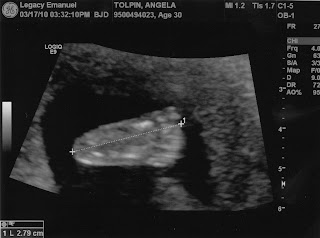

Ultrasound Results